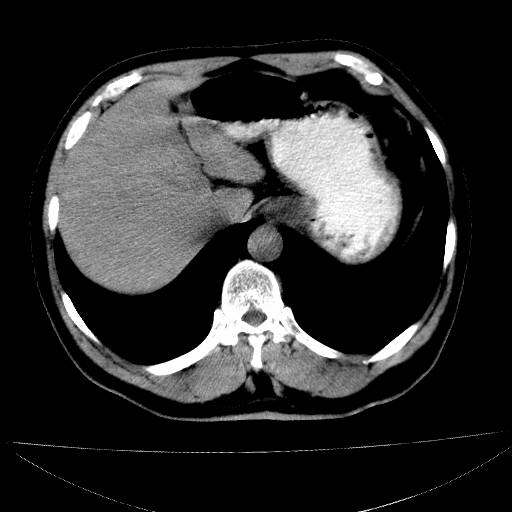

武兄,您是不是玩儿的太玄了些?就一张图片,而且是“三无”产品啊,怎么给您诊断?单就图像说,没有发现什么异常。

虽说只发了一幅,但图像够清晰,再接再厉,暂时未见异常。